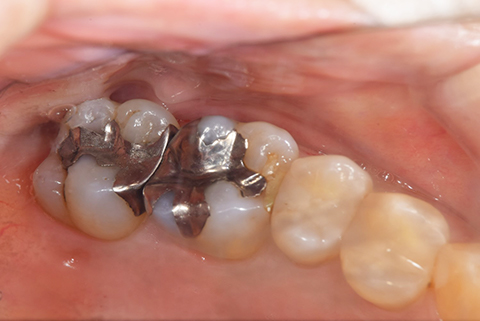

インレー症例

治療前

途中経過

治療後

年齢・性別 43代・女性

主訴 パラジウムインレー2次カリエスの治療

治療内容 左上6セラミックインレー・

左上7ゴールドインレー

治療期間 10日程度

リスク・副作用 虫歯が深ければ、つけた後しみたり、痛みが出る可能性がある。 その場合は神経をとる処置をする。

歯ぎしり、くいしばりでセラミックインレーが割れることがある。

費用 セラミックインレー 55,000円

ゴールドインレー 88,000円